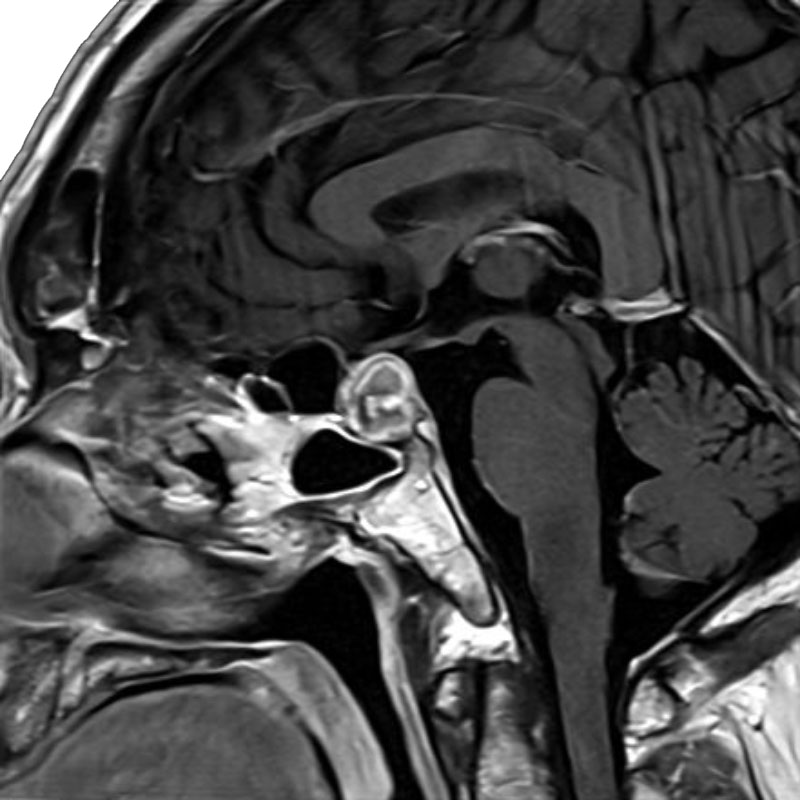

癒着性くも膜炎+脊髄空洞症

空洞-くも膜下腔シャント術

乾/長尾/殿元/青木